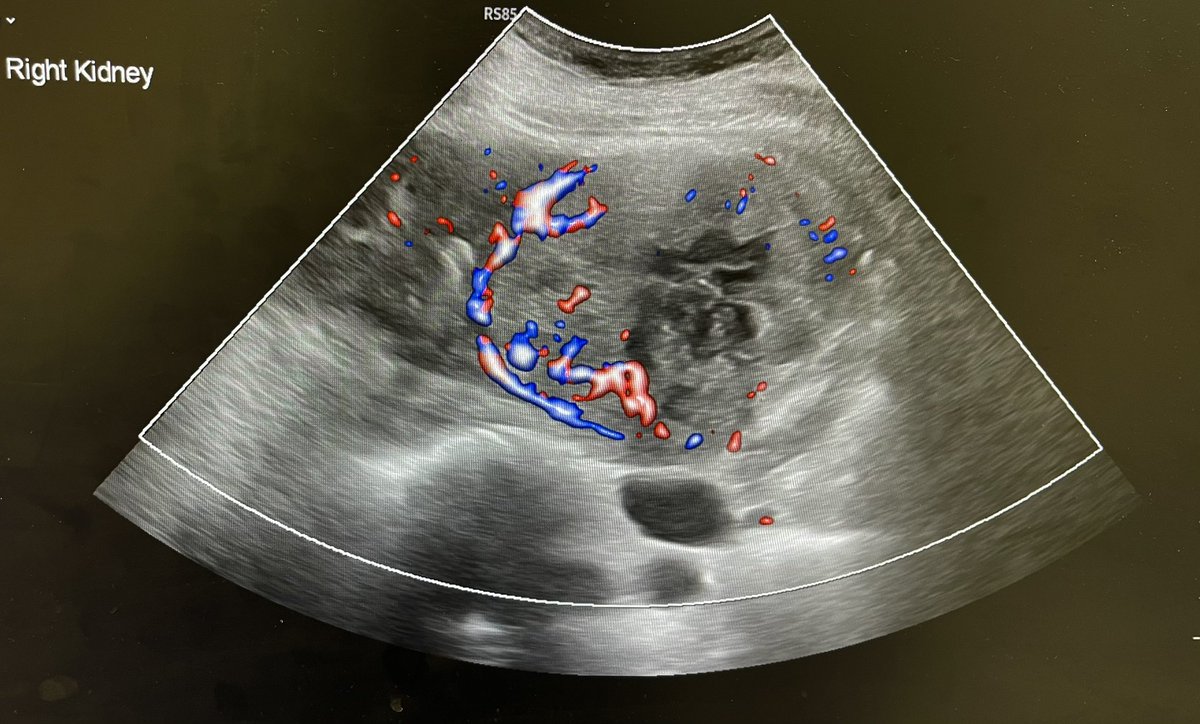

54F with right flank pain and haematuria. Solid heterogeneous right renal mass with vascularity. ? Renal cell carcinoma. @Rad_Munagi @AjuboDaso